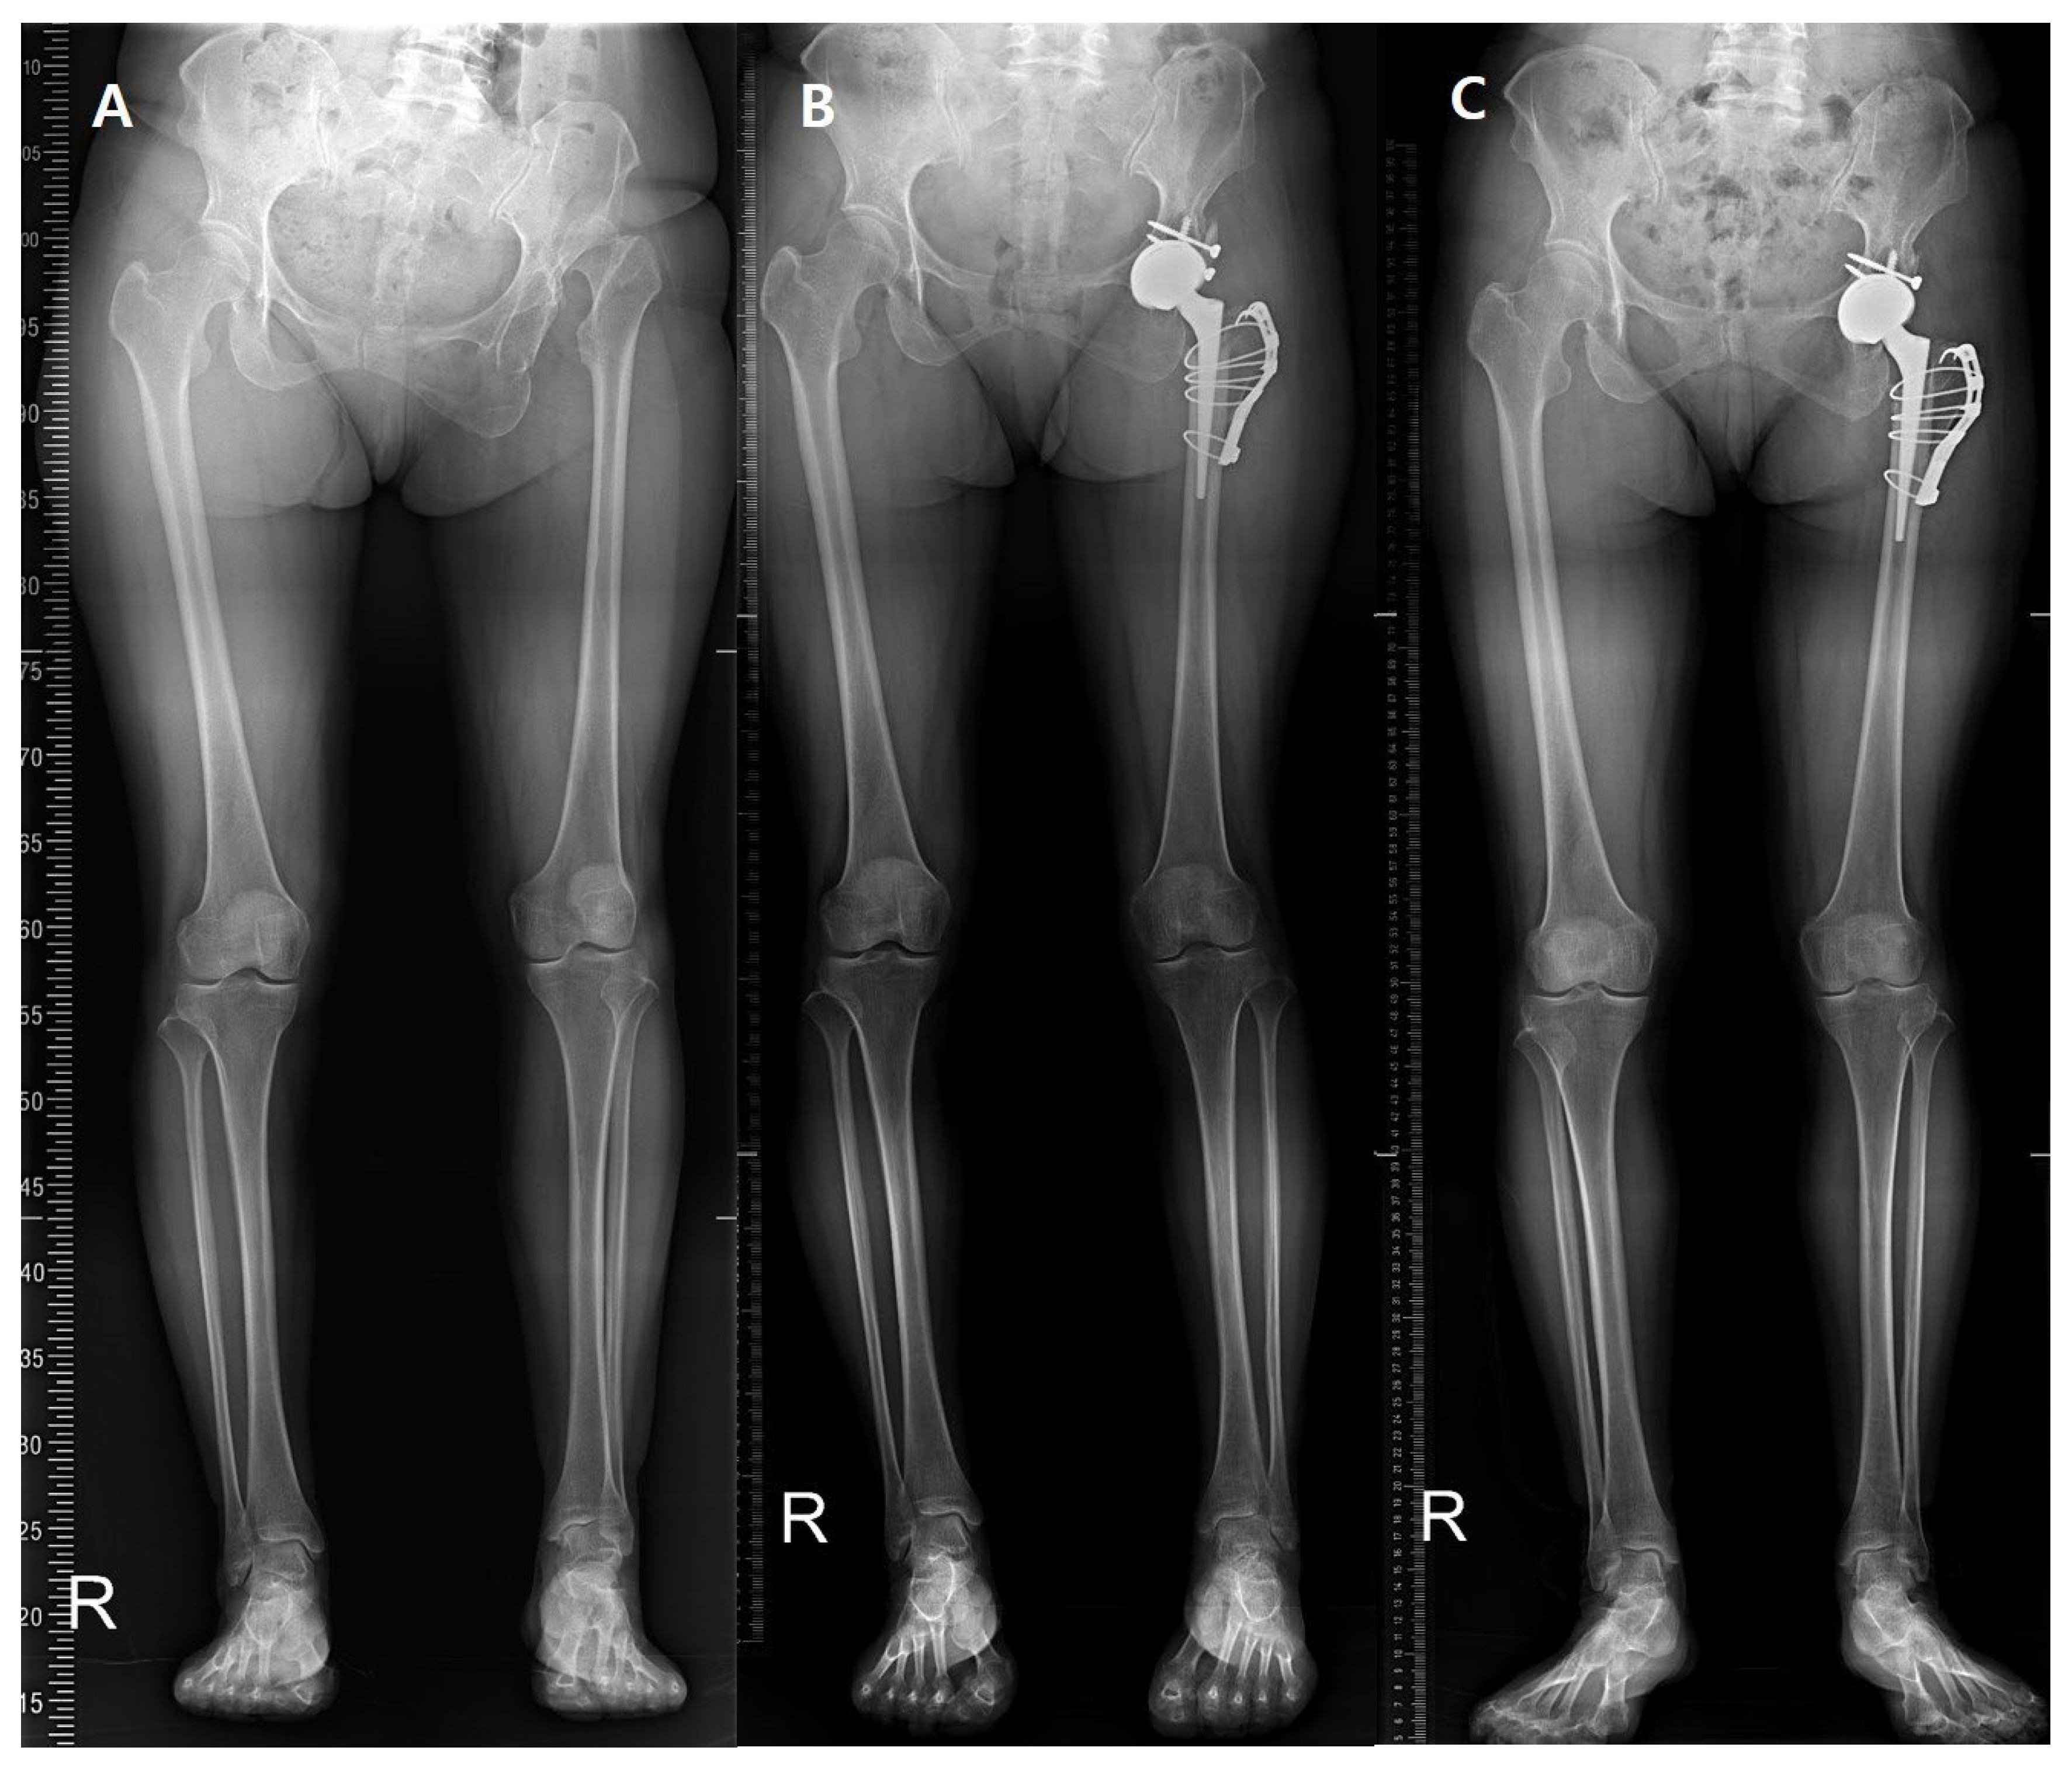

Figure 1.

(A) Preoperative teleroentgenogram of a 50-year-old female with high hip dislocation due to DDH. (B) Postoperative 1-year and (C) postoperative 5-year X-rays.